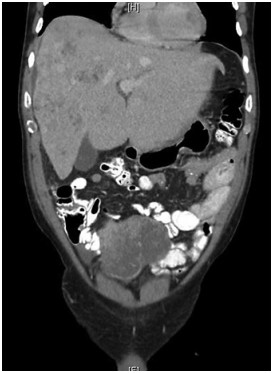

Abstract: Leiomyosarcomas (LMSs) are extremely rare and comprise only 1.2% of small bowel malignancies. Advancements in immunohistochemical techniques have allowed for the differentiation between LMSs and gastrointestinal stromal tumors. LMSs remain difficult to detect via endoscopy and require a more intricate diagnostic approach. The staging and sizing of these tumors are important prognostic indicators. We report a case of a 67-year-old male who presented with bulging lower extremity veins, abdominal bloating, and weight loss. A CT of the abdomen and pelvis revealed a pelvic mass arising from the small bowel and a metastatic hepatic lesion, which was found to be compressing the inferior vena cava. A biopsy of the hepatic lesion confirmed the diagnosis of metastatic LMS.